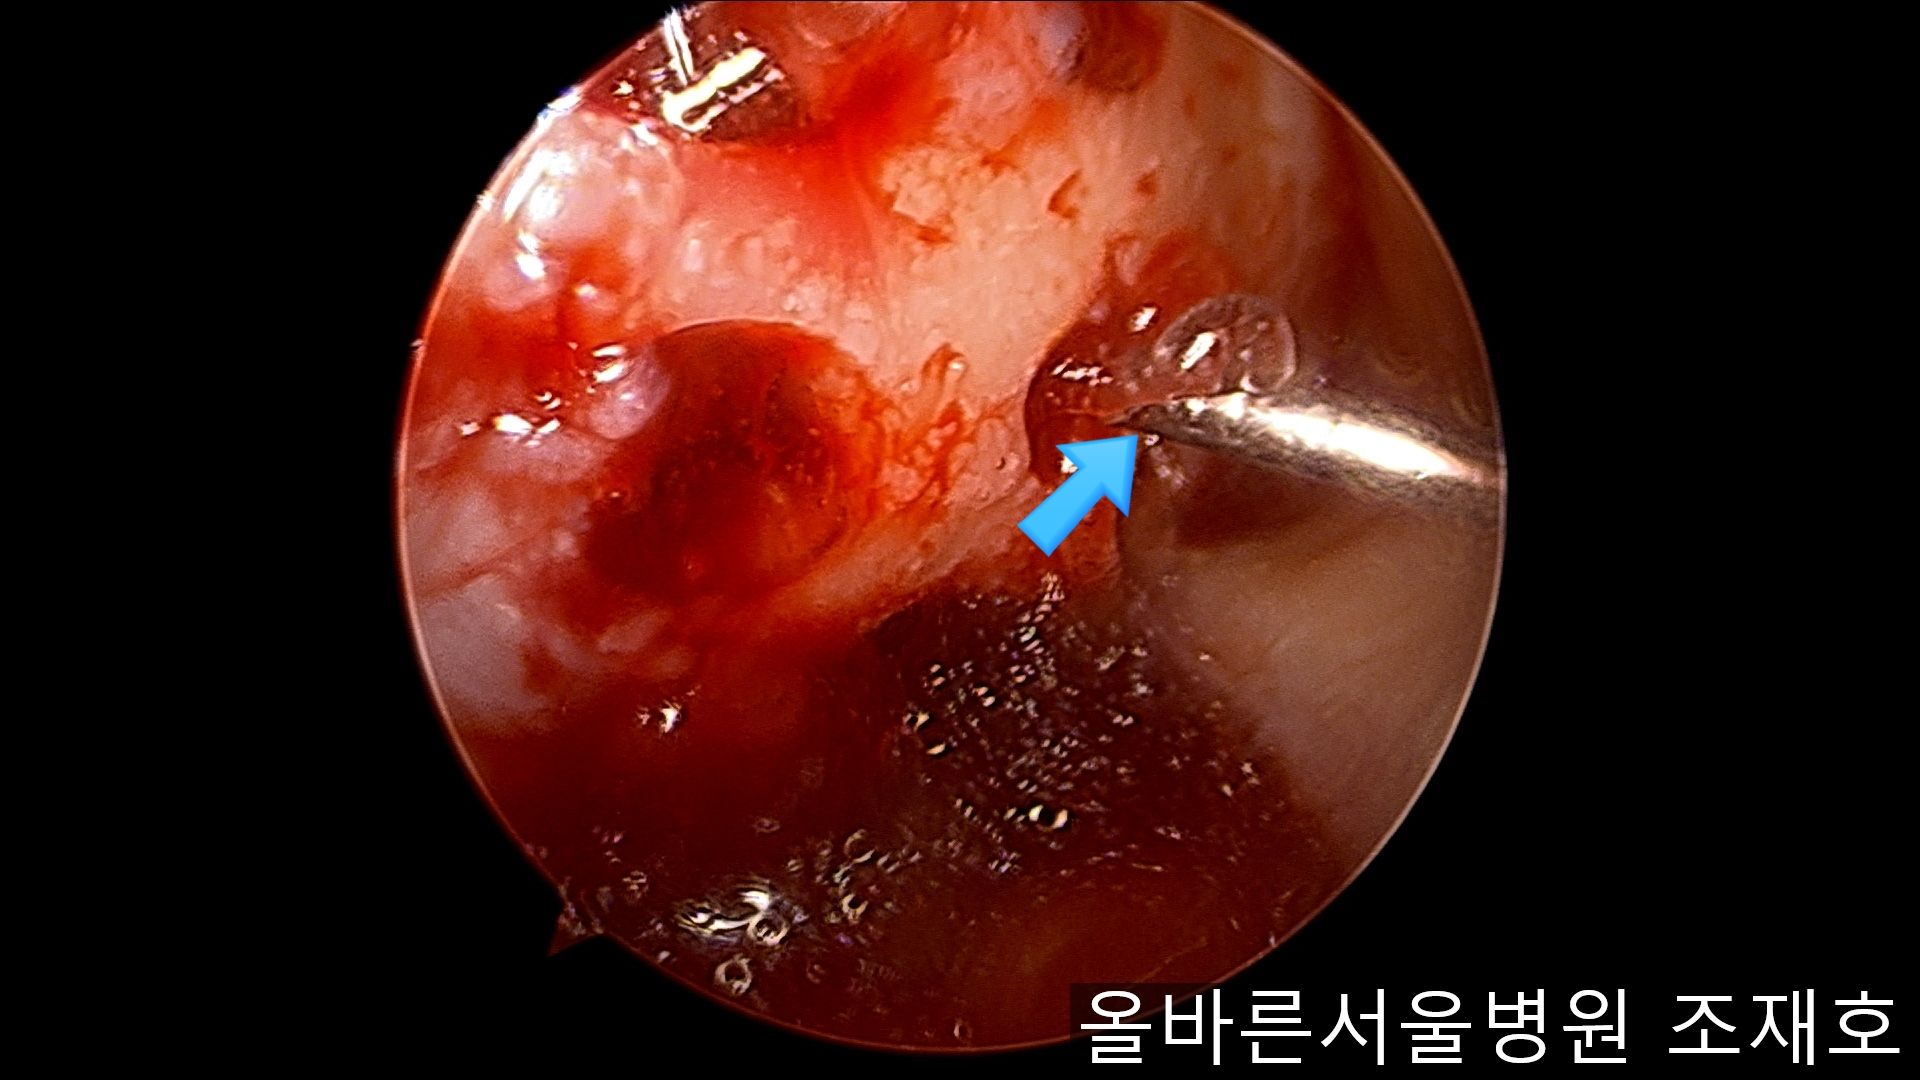

通过关节镜图像可看到:由于内侧股骨髁软骨损伤骨头已经显露出来。

image_9824311181519375935940.jpg

胫骨上端的软骨损伤严重,也露出了骨头。

image_9926851221519375935929.jpg

正是缺失软骨的部位碰到一起,引发剧烈疼痛,腿部逐渐变形。